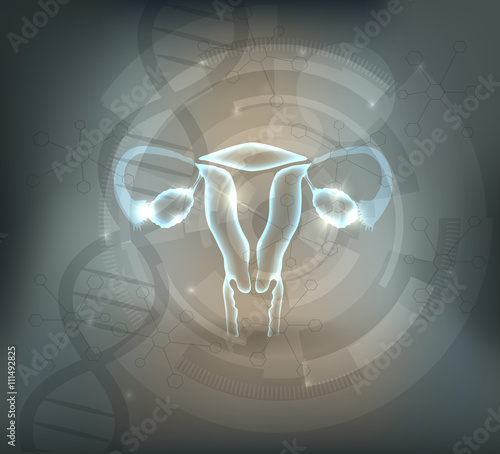

- Naučné plakáty pro školy

- Lékaři